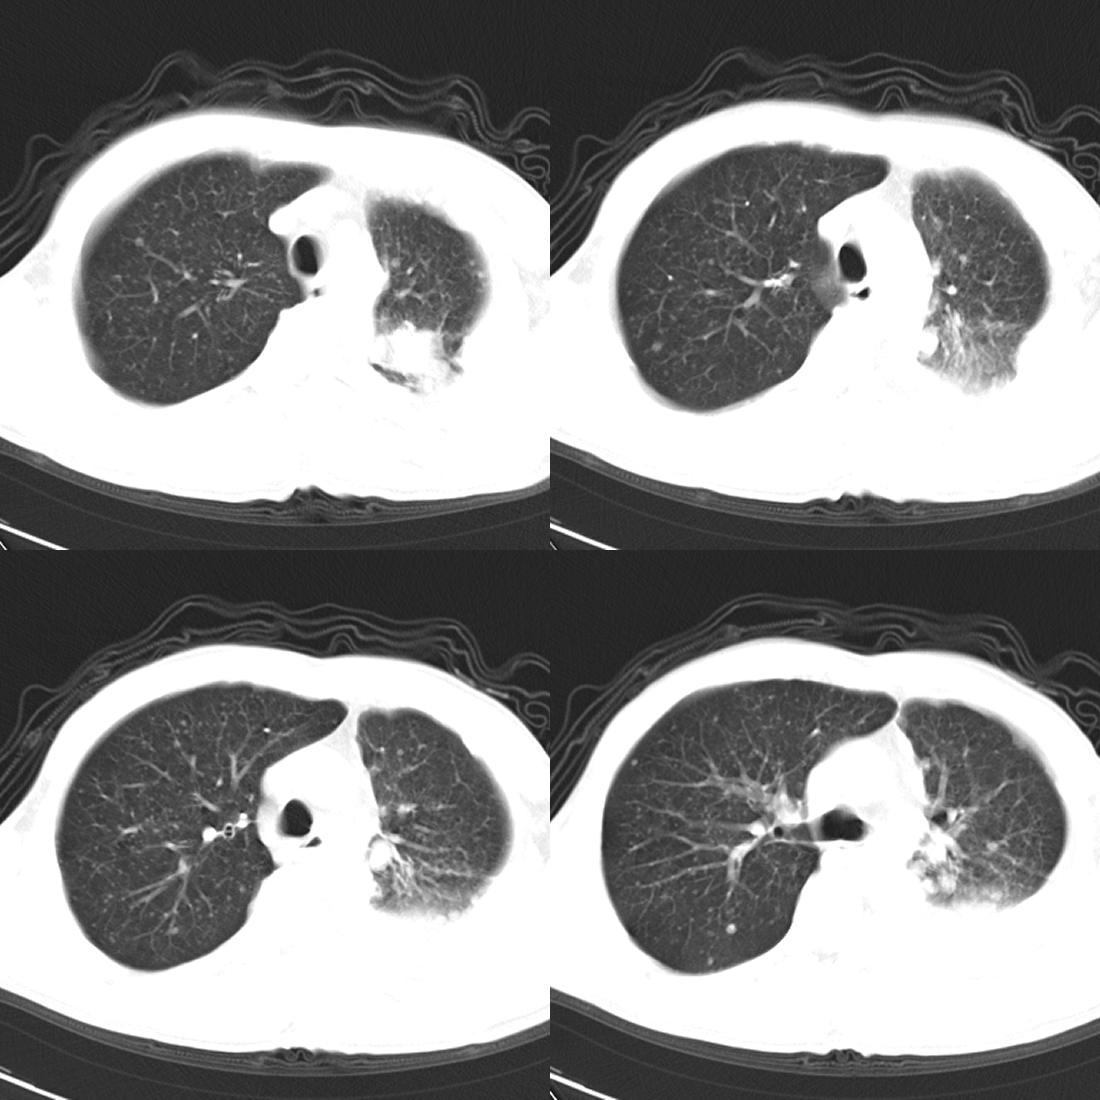

左肺上叶周围型肺癌伴肺\\胸膜\\肋骨\\胸椎横突转移,左侧胸腔积液.

左侧椎体、横突、肋骨呈溶骨性破坏,半左侧胸腔中等量积液;左肺尖部可见一肿块影,边界欠清;多考虑恶性骨肿瘤,不除外肺尖部转移性表现可能。

左肺上叶周围型肺癌伴双肺\\胸膜\\肋骨\\胸椎横突转移,左侧胸腔积液.